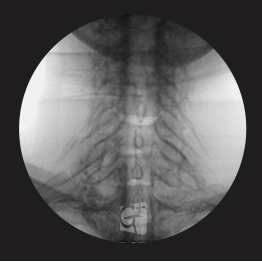

요추 신경성형술

꼬리뼈 구멍으로 카테타 삽입

척추관 안쪽으로 진입 약물 주입

원인부위 염증 제거 및 유착 박리

유착박리로 추간공 확보, 신경 압박 감소

척추관에서 약물이 잘 퍼져나오는 모습

허리 신경 전체를 효과적으로 치료